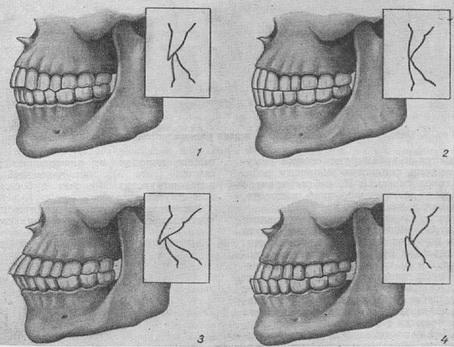

Аноним Пнд 30 Сен 2013 21:18:25  #26 №55608379

1380565404284.jpg

Как на верхней-левой картинке? Это же норма.